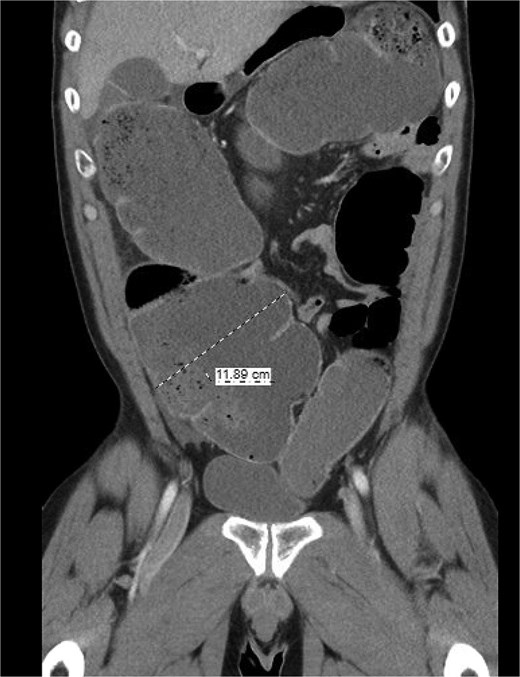

The patient was a 49-year-old male with a past medical history of anxiety and constipation who originally presented to the emergency department complaining of 1 day of worsening generalized abdominal pain, obstipation, nausea, and chills. Of note, he had undergone a colonoscopy 3 months prior to presentation, where two benign polyps were removed. There were no signs of inflammatory bowel disease. Upon examination, he was noted to be tachycardic to 130, with a blood pressure of 90/70 after 2 L of intravenous fluid resuscitation. His abdomen was distended and diffusely tender with peritoneal signs. Laboratory analysis showed a white blood cell count of 26 000, creatinine of 1.8, and a lactic acid of 7.9. A CT of the abdomen/pelvis revealed a cecum of 12 cm filled with liquid stool, but no pneumoperitoneum, pneumatosis, or colonic wall thickening. Figures 1 and 2 demonstrate the axial and coronal images of the dilated colon, respectively.

Axial imaging demonstrating significant colonic dilation. There was no evidence of pneumatosis or pneumoperitoneum.